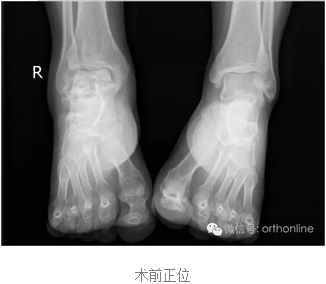

创伤引起的距骨塌陷性坏死一直是医学界面临的难题,治疗手段非常有限,目前只能采用以牺牲踝关节生物学功能的胫-距-跟植骨融合来缓解病人的痛苦,严重影响患者生活质量。

塌陷性距骨坏死一直是踝关节假体置换的绝对禁忌症,该假体打破了常规,为塌陷性距骨坏死提供了非常好的选择。